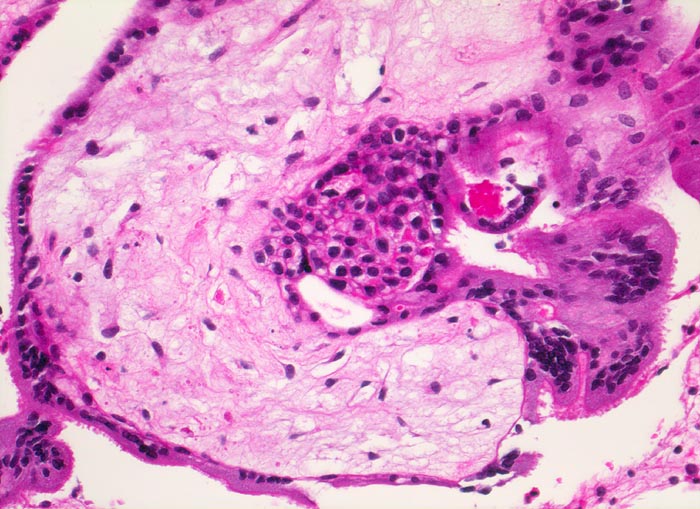

Chromosomenaberrationen verursachen nicht nur beim Feten, sondern auch an der Chorionzotte morphologisch fassbare Entwicklungsstörungen: mangelnde Verzweigungen, wandernde Trophoblastzellen im Stroma, mangelhafte Vaskularisation, hydropische Alteration des Stromas und herdförmige Atrophie oder auch Hyperplasie des Trophoblasten sind typische Befunde bei einer Chromosomenaberration. Aborte mit Triploidie zeigen in der grossen Mehrzahl das Bild einer Partialmole. Eine Tetraploidie kann das Bild einer Windmole (=Windei), einer Embryonalmole oder seltener einer Partialmole verursachen. Autosomale Trisomien können ebenfalls als Windmole oder als Embryonalmole imponieren. In nur etwa 25% aller Spontanaborte sind bei der pathomorphologischen Untersuchung ein Embryo, Embryofragmente oder ein Nabelschnuranteil nachweisbar. Die morphologische Untersuchung des Abortmaterials stellt eine wichtige Ergänzung zu den klinischen Befunden dar.

• Vergrösserte Plazentarzotten mit hydropischem Zottenstroma.

• Vereinzelt Zytotrophoblasteinschlüsse im Stroma.

• Vorwiegend einschichtiges Zytotrophoblastepithel ohne Atypien und mehrkerniger Synzytiotrophoblast. Physiologische polare Trophoblastproliferate.